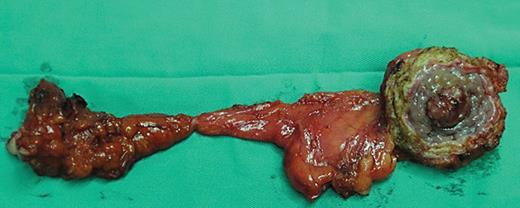

Abdominal ultrasonography, computed tomography (CT), and cystoscopy would be the main tests for diagnosing urachal tumors. Fifty-one patients underwent abdominal ultrasonography and the most common finding was a mass observed at the dome or frontier wall of the bladder (98.08%). CT scans were performed in 44 patients. Of these patients, there were 41 cases (93.18%) with a solid mass and 3 cases (6.82%) with a cystic mass. Calcification was observed in 10 cases (22.73%) (shown in Fig. 1a–c). A total of 46 patients underwent preoperative cystoscopy or biopsy, with the most common intraoperative description being a predominant manifestation visible in the top midline or the anterior wall of the bladder. Malignant tumors were found at the dome of the bladder by magnetic resonance imaging in 4 cases (shown in Table 2).

a–c CT images show a solid mass in the dome of the bladder with calcification. CT, computed tomography.